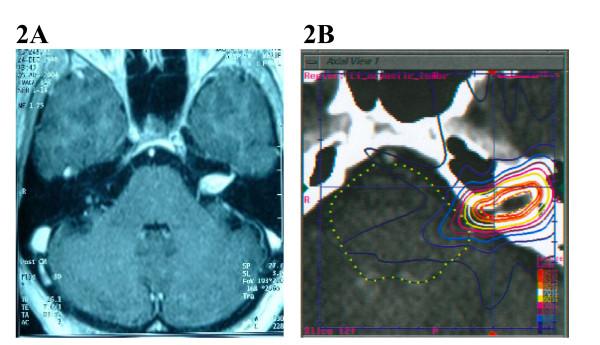

Tumors of the skull base pose unique challenges to radiosurgical treatment because of their irregular shapes, proximity to critical structures and variable tumor volumes. In this study, we investigate whether acceptable treatment plans with excellent conformity and homogeneity can be generated for complex skull base tumors using the Cyberknife radiosurgical system.

At Georgetown University Hospital from March 2002 through May 2005, the CyberKnife was used to treat 80 patients with 82 base of skull lesions. Tumors were classified as simple or complex based on their proximity to adjacent critical structures. All planning and treatments were performed by the same radiosurgery team with the goal of minimizing dosage to adjacent critical structures and maximizing target coverage. Treatments were fractionated to allow for safer delivery of radiation to both large tumors and tumors in close proximity to critical structures.

The CyberKnife treatment planning system was capable of generating highly conformal and homogeneous plans for complex skull base tumors. The treatment planning parameters did not significantly vary between spherical and non-spherical target volumes. The treatment parameters obtained from the plans of the complex base of skull group, including new conformity index, homogeneity index and percentage tumor coverage, were not significantly different from those of the simple group.

Our data indicate that CyberKnife treatment plans with excellent homogeneity, conformity and percent target coverage can be obtained for complex skull base tumors. Longer follow-up will be required to determine the safety and efficacy of fractionated treatment of these lesions with this radiosurgical system.